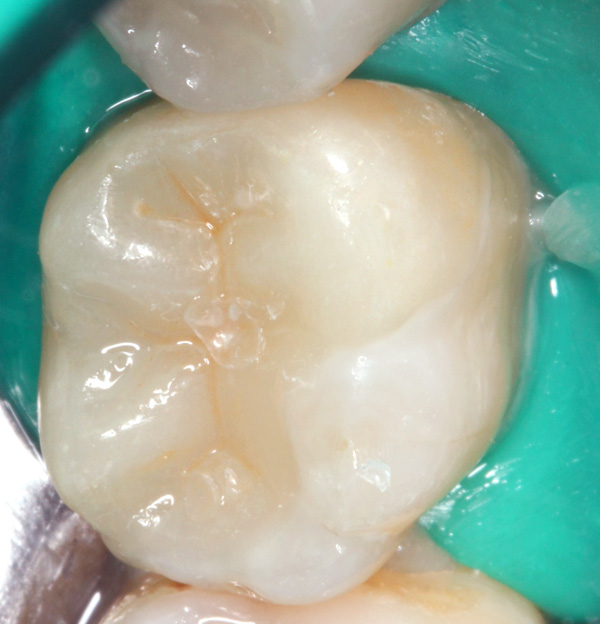

36 Anprobe

36 eingeklebt